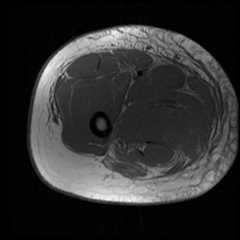

Figure 1.

Axial tau fast spin echo (FSE) of the right thigh demonstrating normal musculature with extensive subcutaneous and subfascial edema. [Powerpoint Slide]